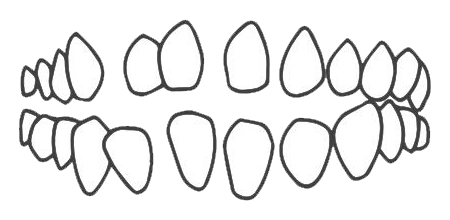

牙列间隙过大

深覆盖

牙列拥挤

深覆颌

开颌

前牙反颌